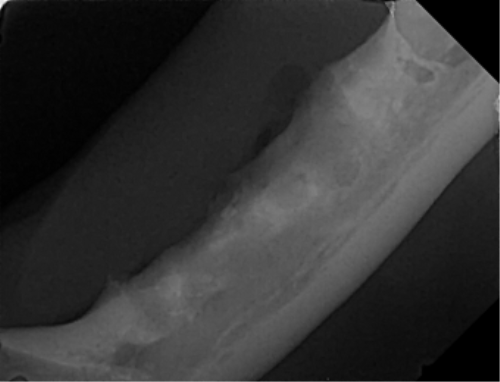

| 치료과정 | -다행히 상추는 금세 포획이 되어서 2번 시도 만에 병원으로 데려갈 수 있었습니다. -많이 마르고 구내염이 꽤 지속된 상태로 보여 검사 후 수술을 진행하기로 했습니다. 방사선, 초음파, 혈액검사를 진행했고 검사상 감사하게도 수술이 가능한 수치가 나왔습니다. 더 못 먹고 염증이 지속될 경우 건강이 더 상할 것 같아 바로 수술을 진행하였습니다. -진통 패치 및 진통제, 항생제 처방을 해주시고 먹는 것을 병원에서 관찰해주셔서 소식을 전해 들을 수 있었습니다. 아이는 첫날 조금밖에 먹지 않았으나 다음날부터 습식에 비벼 준 사료 등을 두 그릇씩 먹으며 씩씩하게 지내주었습니다. 병원 케어를 좀 더 받았으면 하여 일주일 정도 입원을 하였고 피하수액 등을 하여 탈수도 교정이 좀 되었으면 하는 심정이었습니다. -병원에서 마취 상태에서 입 안 사진을 찍어 기록한 후 보여주셨는데 꽤 심각했습니다. 목구멍 쪽 증식한 염증을 많이 절제하였고 레이저 치료까지 진행하였습니다. 치아 엑스레이 촬영도 모두 보내주셔서 기록해두는 데 도움이 되었습니다. -아이가 자발 식이를 잘 할 경우 퇴원을 해도 되기에 집에서 회복 공간을 만들어주었습니다. 나가고 싶은 듯 바깥을 보며 처음에 힘들어했지만 점차 적응하며 편안하게 휴식을 했습니다. 밥은 꼬박꼬박 두 그릇 넘게 챙겨 먹었고 소화가 잘 되는 습식 위주로 주었습니다. 건사료를 언제쯤 먹을 수 있나 관찰하려 두었더니 며칠 안에 금세 먹었습니다. 알갱이 작은 사료를 주었으나 기존에 먹던 맛을 먹고 싶은지 그것만 먹었습니다. |

| 대상묘 치료중 사진 |          |